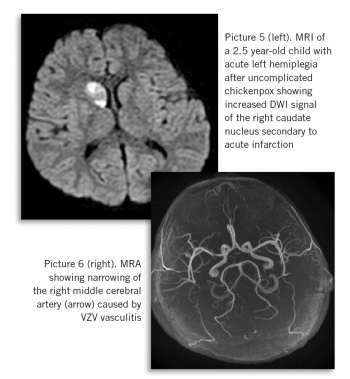

In contrast to bacterial super-infection, neurological complications (see Picture 5 and 6) of chickenpox caused by virus reactivation or post-inflammatory, typically present after a delay, at a time distant from chickenpox infection, making the diagnosis more challenging. Risk of chickenpox complications is increased in children less than one year or over 15 years old, in pregnant women and in the immunocompromised. However, the majority of complicated chickenpox cases occur in previously healthy children.